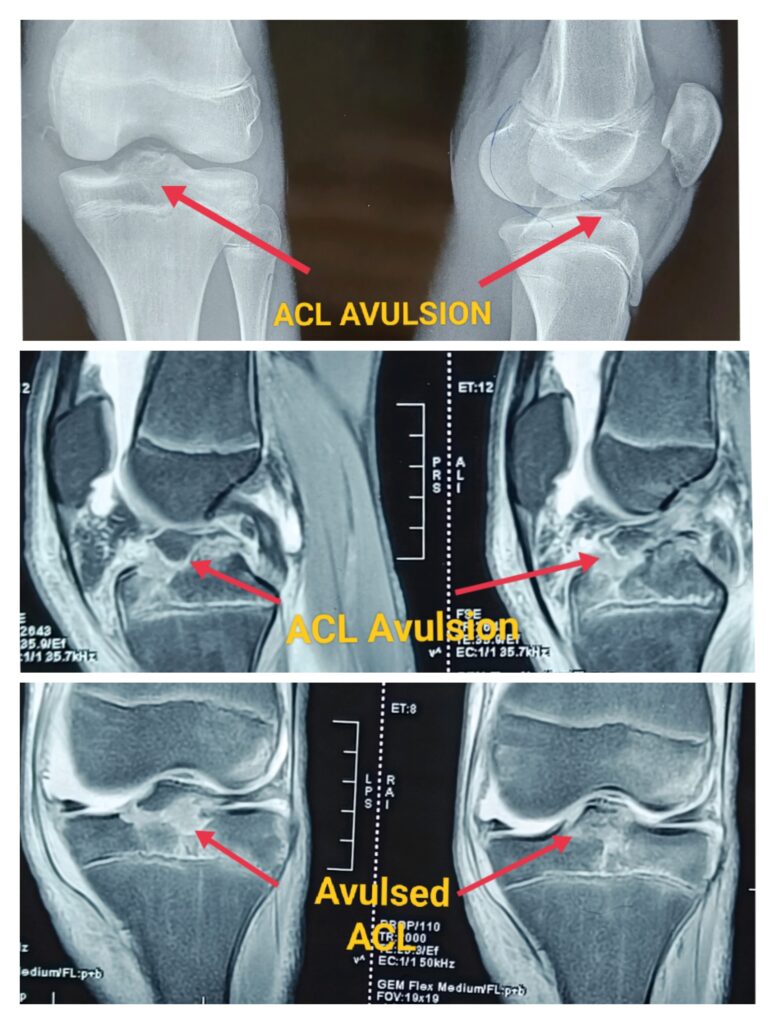

ACL Avulsion

Anterior cruciate ligament (ACL) avulsion fracture or tibial eminence avulsion fracture is a type of avulsion fracture of the knee.Its separation of distal attachment of ACL with bony piece from tibia.

It is more common in children than adults. In past these injuries used to be treated nonoperatively, this leads to significantly disability if left untreated.